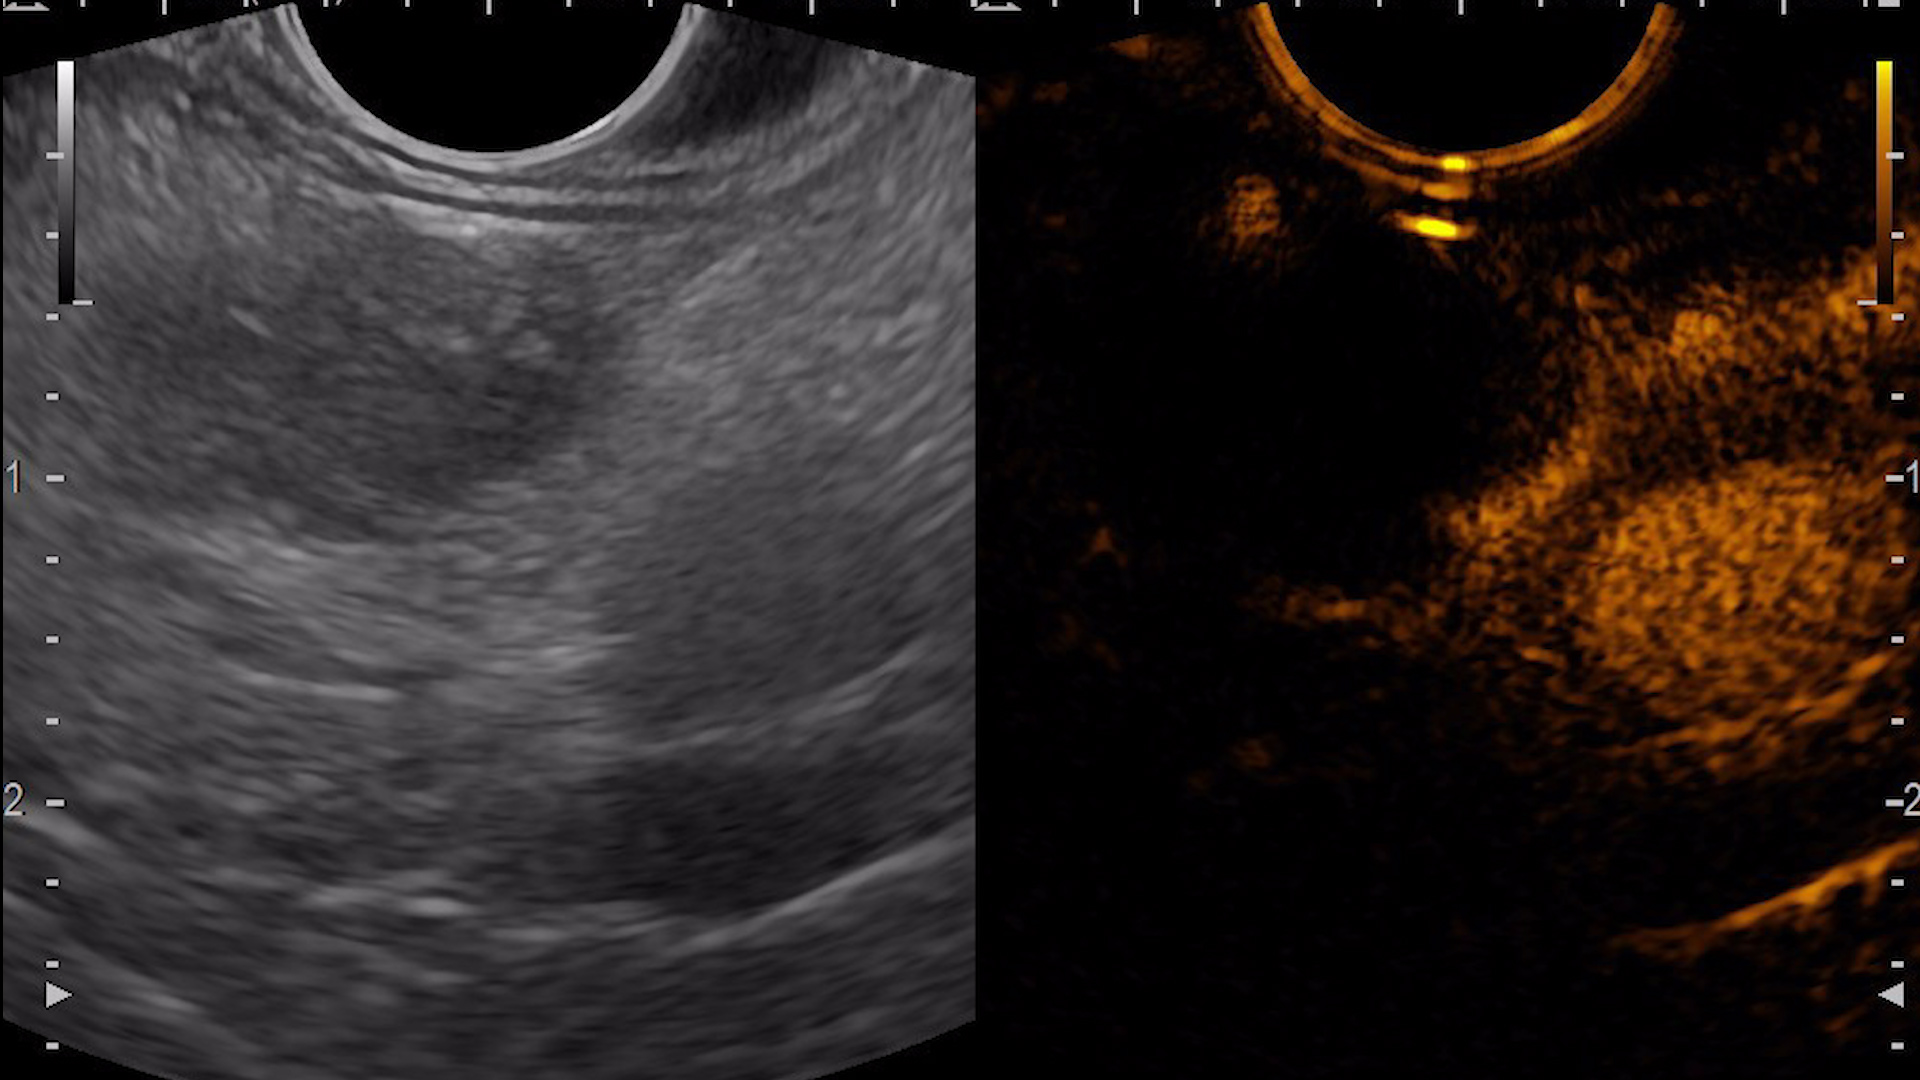

Consequently, an endoscopic ultrasound examination was carried out with tissue acquisition from the mass using a 22G Franssen-type needle (Acquire, Boston Scientific). The tumor was hypervascular on both color Doppler (Fig. 3a), detective flow imaging (Fig. 3b) and contrast-enhanced harmonic imaging (CHI) endoscopic ultrasound (Fig. 4). Histopathology was conclusive for a well-differentiated G1 neuroendocrine tumor, while immunohistochemistry confirmed the diagnosis, showing a Ki 67 index of 1%.